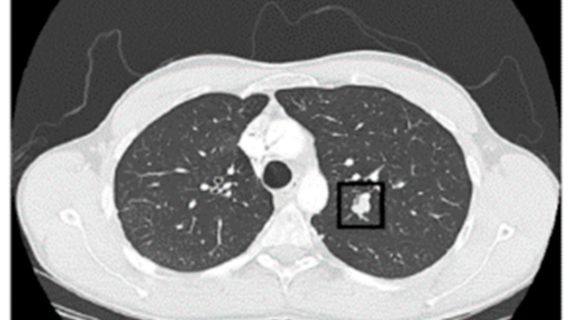

CT Lung Data for Diagnosis

Next, we got this fresh image showing how CT lung data is used for diagnosing lung cancer. The top CT lung dataset from the LIDC database is a game-changer when it comes to making accurate diagnoses and developing personalized treatment plans. This data is like a treasure trove of insights that can help us combat lung cancer like never before.

From CT Lung Data To Lung Cancer Diagnosis. (Top) CT Lung Dataset From

lung dataset lidc diagnosis